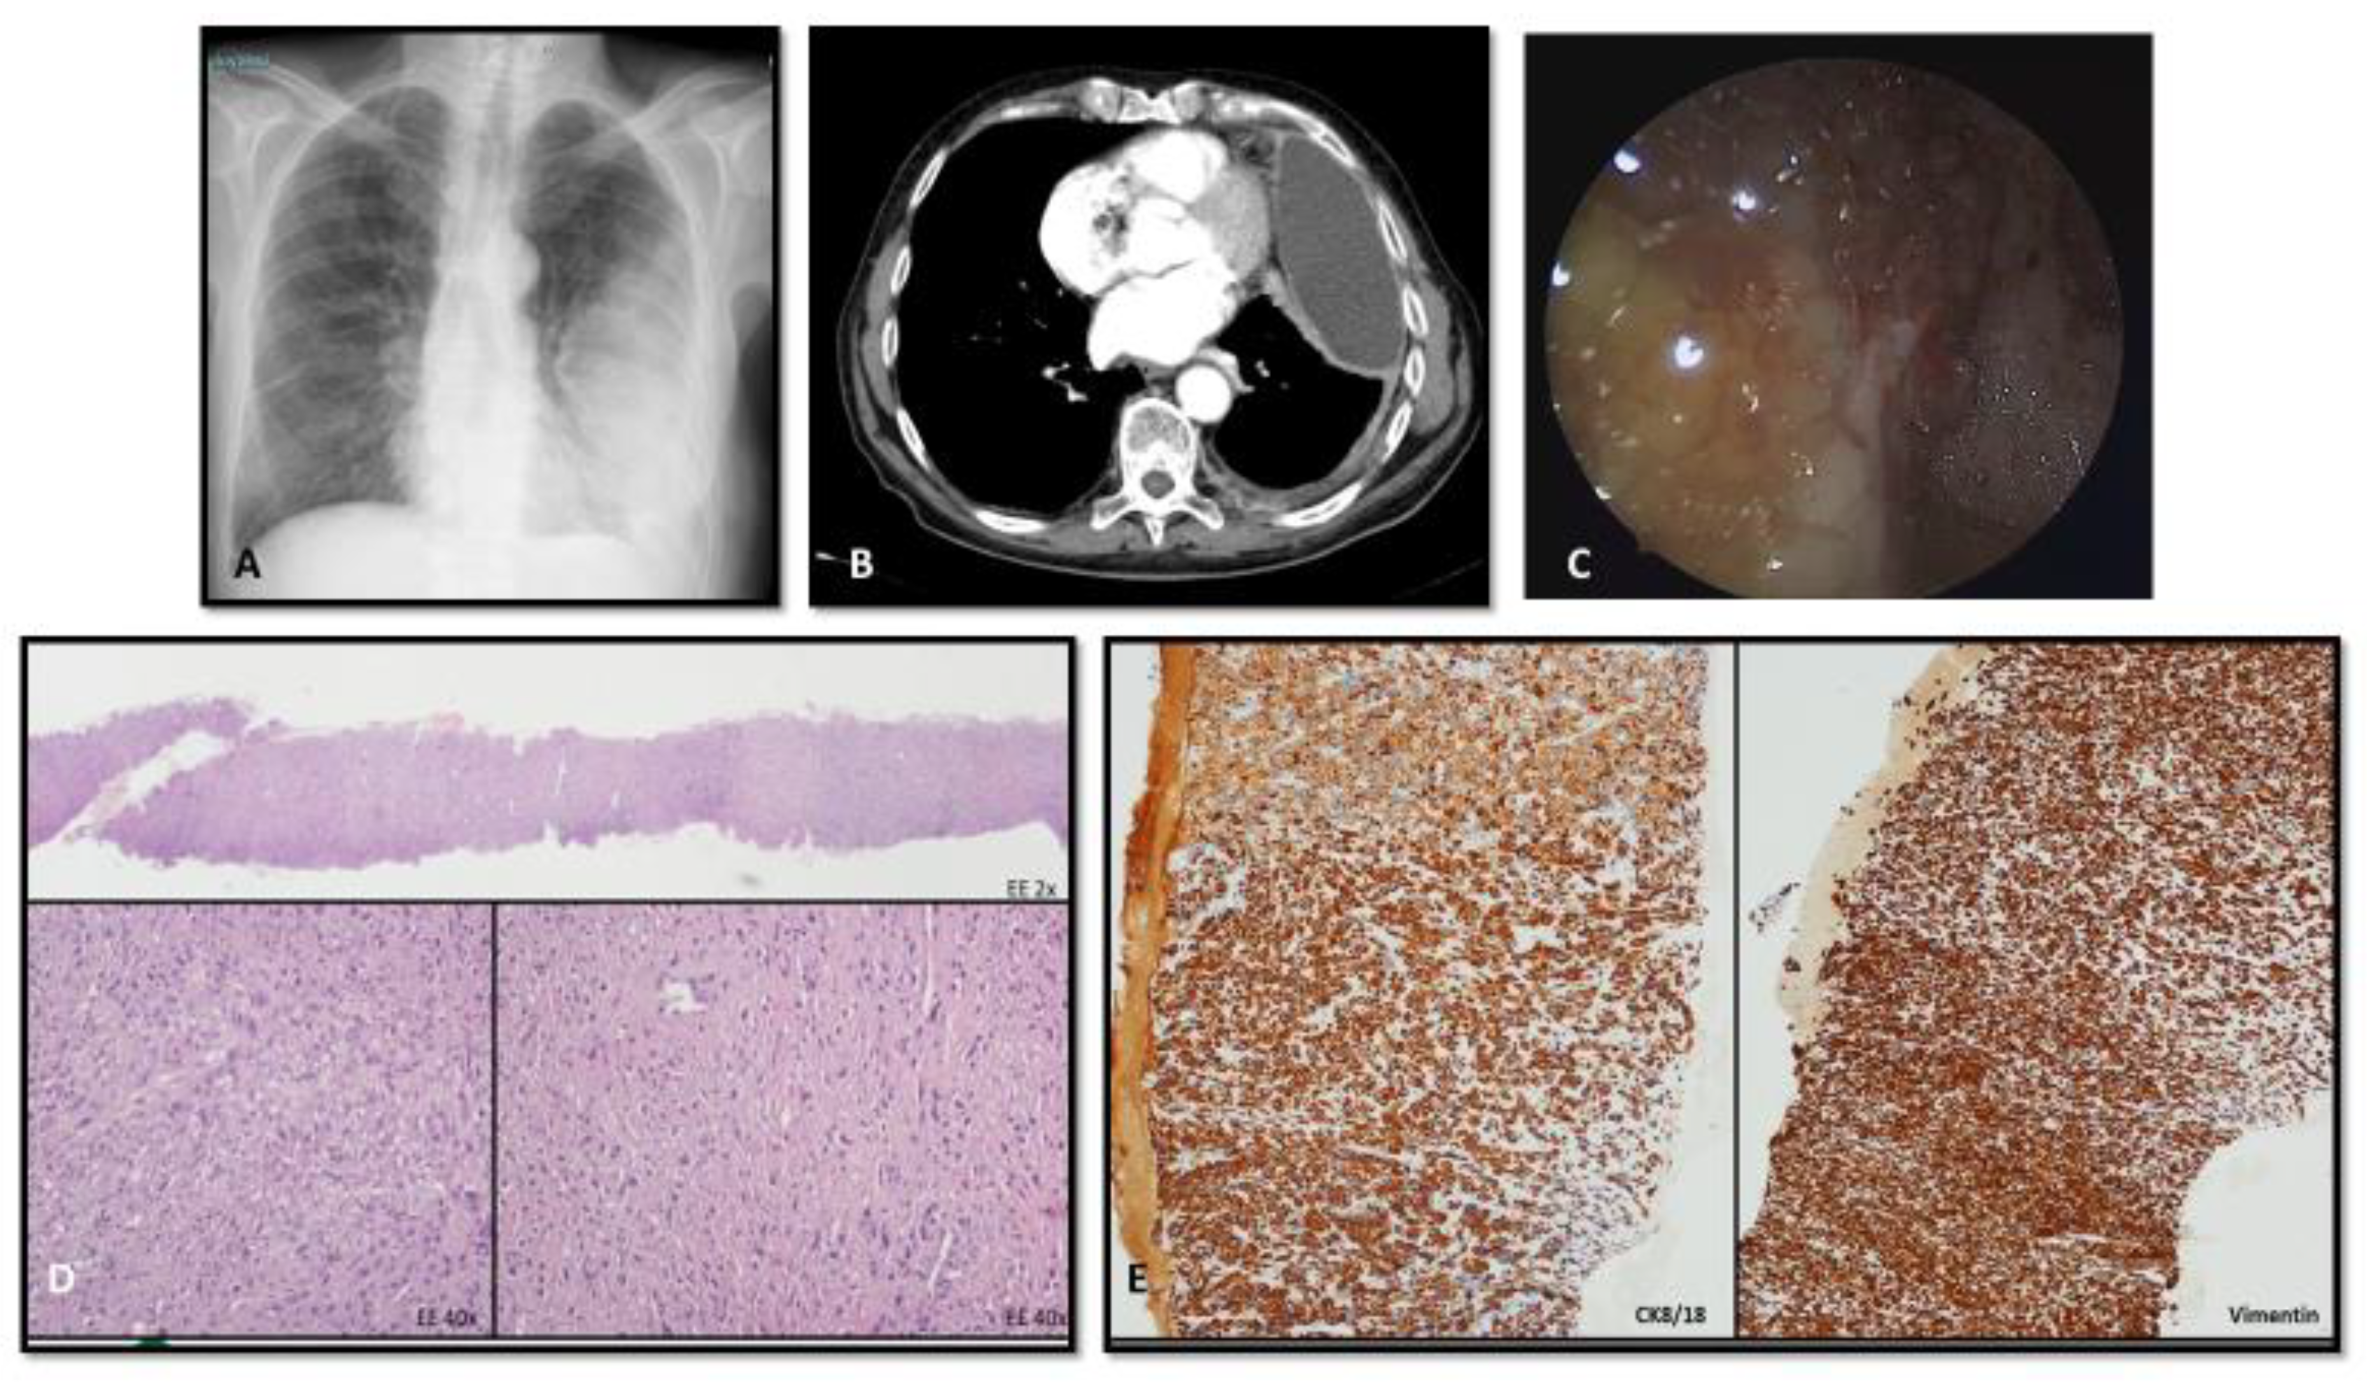

4.2. Imaging

4.3. Bioptic Procedures

4.4. Pathologic Classification and Staging